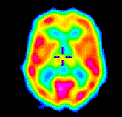

Right-Handed Smokers Sought for Brain Image Study

pet Azaz jobbkezes dohányosokat keresnek, hogy majd agyukról mindenféle képeket készítsenek. Igen jó agyképeket lehet látni a montréali egyetem neurológiai osztályán. Van néhány igen kitűnő mozgóképes darab is. Nem is hinnéd, milyen érdekes az agyad…